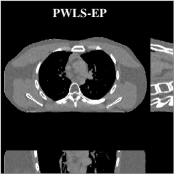

Fig.Β 7 shows the reconstructions (shown for the central axial plane in the 3D volume) for FDK (provided by GE Healthcare), PWLS-EP (corresponds to Fig.Β 8(a)), and PWLS-ULTRA with (corresponds to Fig.Β 9(a)). The PWLS-ULTRA reconstruction has lower artifacts and noise. Moreover, the image features and edges are better reconstructed by PWLS-ULTRA than by PWLS-EP or FDK.

Fig.Β 8 shows the reconstructions (shown for the central axial, sagittal, and coronal planes in the 3D volume) for PWLS-EP with different regularization strengths , denoted as a multiplicative factor of the parameter value in Fig.Β 7. Fig.Β 9 shows the reconstructions for PWLS-ULTRA (with patch-based weights) with different parameter combinations. For the sagittal and coronal planes, we show the central out of axial slices. Larger regularization strengths would achieve more noise reduction but simultaneously lower spatial resolution in PWLS-EP and PWLS-ULTRA, e.g., compare Fig.Β 8 and Figs.Β 9(a) and (d). Larger values of would achieve lower sparsities and more noise reduction but potentially oversmooth the image, e.g., compare Figs.Β 9(c) and (d). Small values of may introduce additional spurious noise in the PWLS-ULTRA reconstruction (compare Figs.Β 9(a) and (b)). Fig.Β 11 shows profiles of chest reconstructions (plotted from the central axial slice) for the PWLS-EP and PWLS-ULTRA methods. The profile locations are shown in green lines in Fig.Β 7. Both PWLS-EP with regularization strength X and PWLS-ULTRA (with patch-based weights) in Fig.Β 9(a) have lower noise than the PWLS-EP with regularization strength X. Though the spatial resolution of PWLS-EP with regularization strength X is close to PWLS-ULTRA in the selected soft-tissue regions, PWLS-ULTRA reconstructs bone and spine areas with higher resolution, and preserves small features better (compare the zoomed-in areas in Fig.Β 8 and Fig.Β 9).